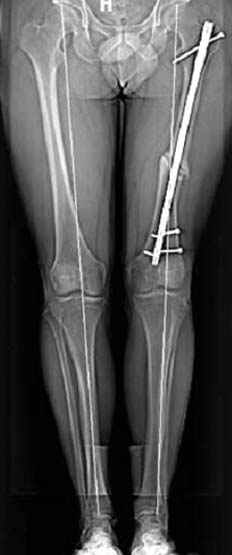

На рисунке N1 предоперационный план лечения ложного сустава шейки бедра- линия ложного сустава, угол и направление введения импланта, клиновидная остеотомия в градусах и миллиметрах, второй снимок после коррекции, расчет, на сколько удлиняется конечность и размеры импланта;

N3 рисунок окончательный снимок, после операции моя рентгенограмма должен выглядеть примерно как эта картина. На N4 снимке клин перед удалением; N5 послеоперации 3 нед.; N6 окончательная рентгенограмма.

(доложен в Ст. Петербурге 2003 и в Москве 2004)

варус при проксимальном отделе 95 градусной пластиной.